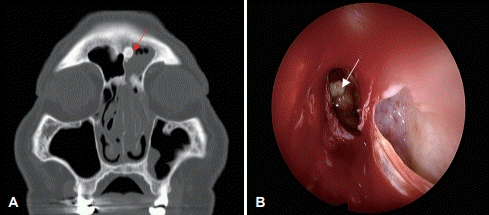

3개월 이상 내과적 치료에도 호전되지 않는 후비루와 후각저하로 64세 남자가 내원하였다. 부비동 내시경 수술을 계획하고 수술 전 시행한 CT의 coronal view(A), 수술 중 시행한 70도 비내시경의 좌측 비강 소견(B)이다. 화살표로 가르키는 소견과 관련된 내용으로 맞는 것은?

해 설 증례는 전두동에 발생한 골종으로 부비동에서 가장 흔히 발견되는 양성종양이다.